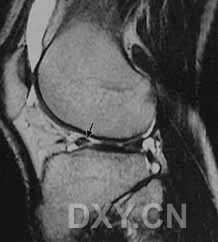

| I级 外侧半月板后角见灶性高信号,不与半月板关节面相接触